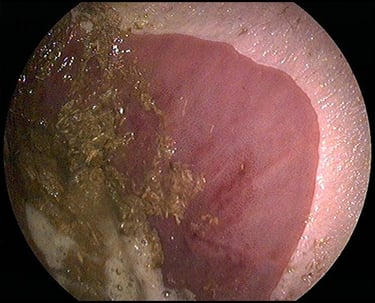

Voor een maagonderzoek (gastroscopie) dient uw paard minimaal 12 uur nuchter te zijn. Na het toedienen van een lichte sedatie voeren we met een camera een inspectie uit van de maag en het begin van de dunne darm.

Bij zowel magere als te zware paarden kunnen aanvullende verteringstesten worden uitgevoerd om na te gaan of er sprake is van een malabsorptiesyndroom of insulineresistentie. Het is belangrijk om te weten dat ook magere paarden in sommige gevallen een vergevorderd stadium van insulineresistentie kunnen hebben.